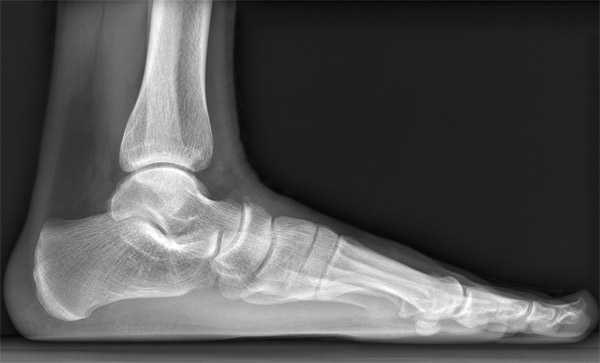

- Рентген тазовой области и нижних конечностей. Данное исследование нужно для того, чтобы проверить состояние органов малого таза и наличие или же отсутствие каких-либо новообразований. Данное исследование необходимо, так как разрастание опухоли влияет на кровообращение, вызывая покалывание и онемение конечностей.

Рентген нижних конечностей